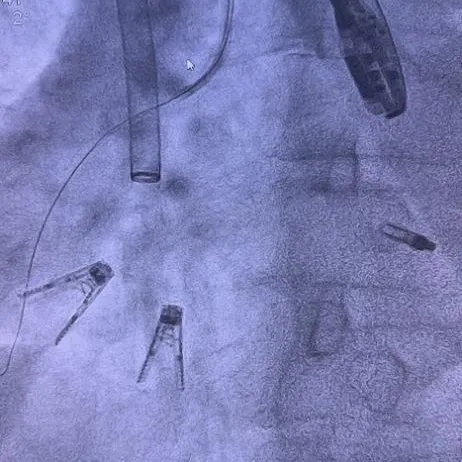

K-Clip®手术过程

麻醉后基线反流

第一套14T夹子指向三尖瓣后瓣环处

攻入锚定螺丝:螺丝攻入三尖瓣环处

准备夹合:调整Orientation

MultiVue贴靠瓣环并关闭夹合部件

第二套器械同样操作,解离后RCA血流通畅

DSA双夹释放后形态无异常,锚定部位均在预期位置,RCA血流未受到影响。